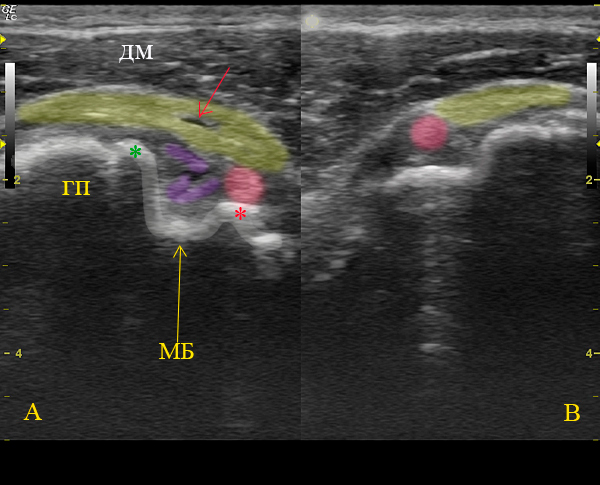

Вот такой получился у меня расклад данного уз-случая.

А:

ГП - головка плечевой кости,МБ - межбугорковая борозда, ДМ- двухглавая мышца,

розовая зона - дислоцированное на уровень малого бугорка сухожилие длинной головки бицепса,

фиолетовая зона - фрагменты поперечной связки плеча, которая образована волокнами из передней поверхности сухожилия подлопаточной мышцы, желтая зона - сухожилие надостной мышцы с участком частичного, линейного разрыва сухожилия.

В:

Сонограмма здорового контролатерального плечевого сустава, представлена для сравнения нормального расположения сухожилия длинной головки бицепса в межбугорковой борозде.

Re: Интересный случай травмы плечевого сустава!

А что показано красной стрелкой и окончательное заключение?